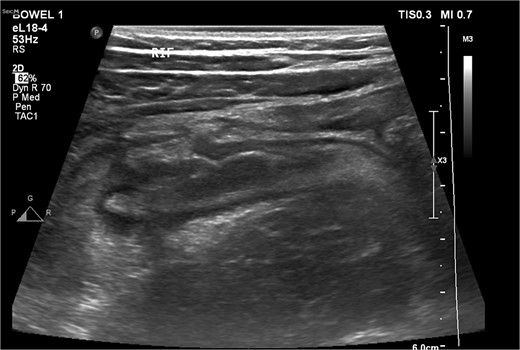

The non-contrast CT scan revealed a retrocecal appendix measuring 11 mm in diameter, with periappendiceal fluid and fat smudging, and reactive thickening of the cecum, indicating uncomplicated acute appendicitis. The patient was admitted to the surgical department and scheduled for a laparoscopic appendectomy (Figs 2 and 3).

CT scan picture with an axial view showing acute inflamed appendix with peri-appendicular fat smudging, confirming the radiological finding of acute appendicitis.